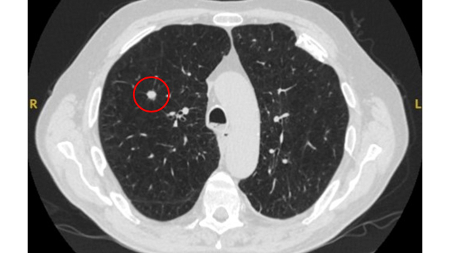

A dense central, laminated, chondroid pattern of calcification (often called popcorn calcification) or a diffuse pattern of calcification strongly suggests that a nodule is benign.[Figure caption and citation for the preceding image starts]: Computed tomography (CT) showing a benign calcified granuloma in the right middle lobe, stable >10 years. The patient reported previous pneumonia on the same sideFrom the collection of Dr George Tsaknis, MD, PhD, FRCP(London), MRQA, MAcadMEd, PGCert; used with permission [Citation ends].

A calculated likelihood ratio for malignancy with a benign pattern of calcification approaches zero.[19] Approximately 10% of malignant nodules have a non-benign pattern of calcification (see E and F).[26][Figure caption and citation for the preceding image starts]: A-D: calcification patterns of benign nodules; E, F: may be seen in malignant nodulesMazzone P.J., Stoller J.K. Semin Thorac Cardiovasc Surg. 2002;14:250-260; used with permission [Citation ends].